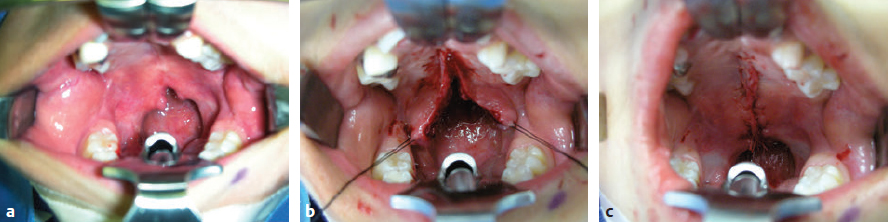

CHAPTER Patients born with cleft lip and/or palate require the care of several specialists and a number of surgical procedures and other interventions, from infancy to adulthood, to achieve total habilitation and have the opportunity to live normal and productive lives. The goals for habilitation include normalization of facial appearance and functions including improvements in soft tissues as well as skeletal, dental, and occlusal relations. Speech, hearing, and psychosocial issues are also addressed and managed. The need for multidisciplinary management using comprehensive protocols designed to address each patient’s multiple and complex needs has been well recognized, and the role of the team approach has become the gold standard of cleft care. Members are responsible for the longitudinal evaluation and coordinated care and provide for regular interactive encounters between all necessary professionals representing a variety of disciplines. They meet to communicate, collaborate, and consolidate knowledge. Extensive initial evaluation plans are made for immediate and future care based on each patient’s individual needs and the team’s treatment protocols. A prime responsibility of each team also includes careful record keeping. Collected data are studied and analyzed periodically to fully appreciate the outcome of protocols and surgical procedures, identify possible drawbacks, and modify or improve them as needed.1 Evaluation of results after cleft lip and palate repair is not easy, and several flaws are recognized in the reported outcomes of retrospective or prospective studies. Nearly 2 decades from infancy to adulthood are necessary for the completion of care and subsequent evaluation of functional and aesthetic results. Thus the final evaluation of outcomes can be problematic for several primary reasons: • Turnover of team members • Change of protocols • Introduction of new surgical procedures • Patients’ relocation • Incomplete records for services provided outside the institutions • Changes in insurance coverage • Denial of insurance coverage for some necessary services and refusal of patients to undergo final aesthetic or reconstructive procedures Many studies include a small number of patients with multifaceted problems related to the deformity, as well as significant variations in treatment protocols, timing for each procedure, surgical technique(s), and experience and skills of the individual surgeon, and many have an incomplete follow-up period.2 Furthermore, the vast majority of current studies rely primarily on subjective, not objective, evaluation. For example, evaluation of facial features using only photographs provides information about facial symmetry, but this may not be the most appropriate way to judge a surgical outcome given that only static results are displayed and asymmetries or irregularities during animation could have been missed. The need for well-planned, well-designed, ethical, multicenter, prospective long-term studies has been well recognized. Such studies could provide quantifiable, nonbiased data and assist in improving patient care by addressing remaining controversial issues, such as appropriate timing for specific surgical procedures as well as selection of the best possible surgical technique(s). Until such studies are available surgeons must rely on data from existing studies and honest evaluation and analysis of their own results to provide the best possible care for their patients. With improved knowledge and collective experience, extensive long-term follow-up studies, appropriate coordinated care, cooperation among specialists, close monitoring, and analysis of short- and long-term results, as well as adequate funding to cover all necessary services, management of patients with facial clefts could further improve so consistently superior results can be achieved. Residual deformities have several primary causes: • Failure to recognize and treat the full spectrum of problems associated with facial clefting • Tissue deficiencies inherent to the cleft • Inappropriate timing • Poorly designed and performed procedures • Complications of the initial surgery Additional operations and revisions are required to correct deformities that were not addressed during the primary procedure, inherent tissue deficiencies, maxillofacial changes, and/or scar contractures. Additional procedures might also necessary to address otologic, dental, and speech problems and to improve persisting residual functional and aesthetic deformities. These procedures have been described at length in many textbooks and scientific articles. The average number of procedures necessary to achieve the best possible functional and aesthetic habilitation has not been clearly defined, and it is difficult to accurately estimate from existing data. In some studies secondary procedures, such as alveolar bone grafts and orthognathic surgery, are barely mentioned or included, and most studies do not include dental or otologic procedures in the average total numbers. Thus the total number of procedures or interventions is definitely underreported.3 Few surgeons have reported on the actual average number of procedures required to achieve the best possible long-term results.4–7 More recently David and others8–10 presented a series of papers entitled “From Birth to Maturity: A Group of Patients Who Have Completed Their Protocol Management” that included evaluation of patients with unilateral cleft lip and palate, isolated cleft palate, and bilateral cleft lip and palate. These unique studies are based on the experience of one surgeon and a center with a relatively stable patient population. Despite the lack of detailed longitudinal data, however, there is general agreement that regardless of protocol of care, subsequent procedures will be necessary from infancy to adulthood to achieve the best possible functional and aesthetic results and complete habilitation. The objectives of primary cleft lip repair are to establish anatomy and symmetry of the upper lip and nostrils and improve form and function. Criteria for satisfactory cleft lip repair, regardless of surgical technique, are summarized in Box 40.1. The value of preoperative orthopedics and lip taping in the final outcome is still debated. Repositioning of the maxillary alveolar segments in an anatomically correct position could facilitate a tension-free closure and allow for a simultaneous periosteoplasty in selected cases. Such an approach might result in a better appearance of the lip, alveolus, and nose and potentially reduce the total number of secondary procedures. At my center we use a modified nasoalveolar molding device to improve the position of the maxillary segments and facilitate nasal repair.11 Intermediate results appear promising, but definitive final long-term results of such interventions and potential adverse effects on maxillofacial growth are only partially available.12–14 Disadvantages of this protocol include the additional expenses and the need for multiple visits for adjustment, but these could be offset by the reduction of subsequent surgical procedures. Summary Box Common Complications Related to Cleft Lip and Palate Repair Cleft Lip Cleft Palate • Dehiscence • Bleeding • Infection • Unfavorable scarring • Discrepancies of the upper lip • Intraoral (mucosal) scar contracture • Orbicularis oris deformities • Mucocutaneous deformities • Vermilion deformities • Sulcus obliteration • Combinations • Dehiscence • Palatal failures/fistulas • Scar contracture • Velopharyngeal deficiencies • Skeletal deformities • Combinations Preoperative orthopedics for bilateral clefts with repositioning of the prominent premaxilla is more widely accepted. Several techniques have been described to achieve premaxilla repositioning. We use a noninvasive appliance, fabricated by our prosthodontist, which is helpful in optimizing the position of the premaxilla and, if needed, combined with nasoalveolar molding extensions. Negative effects on facial growth and development have not been observed. Several weeks are necessary to achieve a favorable repositioning of the premaxilla and improve alignment with the maxillary segments.15 In extreme cases, and when conservative management is unsuccessful, premaxillary setback can also be used to bring the premaxilla within the occlusal plane and facilitate a tension-free lip and palate repair.16 Immediate surgical complications after cleft lip repair are extremely rare but include bleeding, infection, and dehiscence. Early wound dehiscence is rare and primarily is a result of technical errors or closure under tension or occurs after accidental trauma. In such cases, immediate management with minimal débridement, additional undermining as needed, and layered closure without undue tension is recommended (Fig. 40.1). • Detailed markings of all landmarks, taking into consideration the anatomy of the upper lip, alveolus, and nostrils • Accurate measurements and markings of all proposed incisions • Gentle tissue handling • Development of flaps on either side of the cleft with adequate tissue mobilization • Release of superficial and deep fibers of the orbicularis oris from their abnormal attachments • Dissection and reposition of the cleft-side lower alar cartilage in a more symmetrical three-dimensional position • Reconstruction of the nasal floor • Accurate skin, muscle, and mucous membrane union • Closure under minimal or no tension to achieve the optimal scar • Symmetrical vermilion border with alignment of the vermilion (dry lip) and the mucosa (moist lip) • Slight eversion of the lip, accurate reconstruction of the Cupid’s bow and the tubercle, and correct alignment of the white roll • Symmetrical nostril floors and elongation of the columella, as needed Fig. 40.1 (a) A 7-month-old patient 7 days after bilateral cleft lip repair with complete dehiscence on the left side after a fall at home. (b) After cleansing and minimal débridement. (c) The lip was repaired again in layers. (d) Two months later the lip has healed well. Residual lip deformities might vary from minor ones corrected with minimal interventions, to major asymmetries and deformities that may even require complete revision of the lip repair. It is beyond the scope of this chapter to describe all residual deformities and present all reported techniques and modifications. The most common deformities are presented with the recommended treatment and with reliable techniques based on my experience and time-honored procedures. A revision lip surgery should only be chosen after extensive consultation with the family and the child and with a clear understanding of the expectations. Objectives of the procedures, the surgical plan, and possible outcomes should be outlined and false expectations dispelled. Timing can affect the outcome and should be taken into consideration, but decisions should be individualized and not made in a rigid and dogmatic fashion. Procedures should be postponed if an adolescent is not willing to have surgery, even when parents desire and request it. Conversely, some procedures might be scheduled earlier than initially planned if there is evidence of a negative psychologic effect on the child. If possible, several procedures should be bundled to reduce time away from school or work, additional psychological trauma from multiple interventions, and cost. Before planning a revision, the entire lip, including the oral mucosa; sulcus; alveolus; and nostrils should be examined at rest and during animation. The deformity should be analyzed and all contributing factors taken into consideration. All necessary soft tissue landmarks should be appropriately marked and measured. All contributing elements to the deformity should be corrected in one setting whenever possible (Fig. 40.2). Careful planning, appropriate timing, and detailed execution are extremely important, because failure of the revision procedure to correct the deformity may result in additional scarring and tissue loss that could further reduce the chances for adequate habilitation.3,17 Wide, poorly healed persistent scars of the upper lip with unsightly stitch marks are encountered less commonly. They result from closure under tension and the use of tight sutures left in place for too long. Such problems can be avoided in most cases by using fine techniques with meticulous tissue handling and a tension-free closure, fine sutures, or even tissue adhesives. Other aggravating factors include postoperative bleeding, infection around the suture line, and dehiscence. The surgeon should be able to differentiate these unsightly scars from the hypertrophic scars that form without apparent cause and usually fade away slowly without need for additional surgical intervention. Timing for scar revision is important to the final outcome. Waiting several months before a revision to allow the scar to mature is recommended. After careful evaluation, the appropriate surgical procedure should be planned. Elliptical excision of the scar, with precise approximation and closure after limited undermining, is the simplest solution. This technique, however, can only be applied for relatively narrow scars. Excision of wider scars might result in defects that, if directly repaired, might cause distortion of the lip in the vertical or horizontal axis and/or narrowing of the nostril sill. To prevent these problems, the excision should be planed accordingly, preferably with a wavy style of excision, undermining on either side of the defect and performing tissue rearrangement as needed. Geometric tissue rearrangement with z-plasties and other techniques should be avoided, because the subsequent scar will permanently carry the marks of such designs. Dermabrasion is helpful in some cases and is primarily recommended for improvement of residual surface irregularities. Finally, single hair micrografts have been recommended for male patients to further camouflage the lip scar and allow for a moustache.18 An excessively long lip on the cleft side is truly technique related. It has been encountered with LeMesurier and the initial Tennison repairs but can result with other techniques as well. Correction is difficult, because in most instances all lip layers are involved. If the discrepancy is minor, it can be corrected with appropriate excision just below the nostril sill. If a significant discrepancy is present, however, the lip should be completely divided after appropriate markings are made and carefully repaired in layers. Fig. 40.2 The entire lip, including the oral mucosa; sulcus; alveolus; and nostrils should be evaluated and all necessary soft tissue landmarks marked and measured. A short lip results primarily from straight-line closures, inadequate rotation, and advancement techniques and scar contractures. Small discrepancies can be corrected with elliptical, diamond-shaped, or wavy excisions of the entire scar and closure after adequate undermining. If needed, a z-plasty can be designed and incorporated with the revision, preferably below the nostril sill. The drawback to such approaches is the small gain achieved and the addition of a Z-shaped scar on the lip. If a significant discrepancy exists, the only solution is to redo the lip repair, extending the rotation advancement design to increase lip height (Figs. 40.3 and 40.4). Fig. 40.3 (a,b) This 5-year-old had a significant residual deformity of the lip and nose including a short lip, dehisced orbicularis oris, and lateral flaring of the cleft-side nostril. Excess skin of approximately 1-cm width in the horizontal axis was identified during markings. (c) Excess skin with corresponding vermilion was excised, the orbicularis oris was approximated after undermining, and the nostril floor was repositioned after reduction of the skin of the sill. (d) Immediate postoperative result. Fig. 40.4 (a–c) This patient had a significant residual deformity after bilateral cleft lip repair. He had a short lip, no orbicularis contact in the midline, exposed moist mucosa in the vermilion, and bilateral scar contractures in the oral mucosa. (d) Appropriate tailoring of the philtrum, approximation of orbicularis oris muscle fibers in the midline, excision of redundant vermilion, release of intraoral scars, and coverage of the mucosal defect with sliding flaps. (e) Final result 4 months after revision with improved symmetry and balance. The tight upper lip deformity primarily occurs in patients with bilateral clefts. Local tissue rearrangement and even revision of the repair is not beneficial in most cases because of the limited tissue availability and scarring. Because of the paucity of tissue, a flap from the lower lip, an Abbé flap, should be added after all scarred tissue is removed.19 This procedure is not recommended for young children because of the temporary junction of the lips. To achieve a superior functional and aesthetic result and a balanced profile, accurate design of the dimensions of the flap to match the created defect, placement of the flap in the center of the lip to simulate the philtrum, and placement of the final scars to simulate the philtrum columns are necessary. The width of the flap should be adequately planned and narrower from the normal philtrum to encounter for subsequent widening from natural tension. The layers of the flap should be sutured carefully to the corresponding layers of the lateral lip segments and the upper buccal sulcus20 (Fig. 40.5). Fig. 40.5 (a) This woman had a very short and tight upper lip after bilateral cleft lip repair and a subsequent revision. The upper sulcus was completely obliterated. (b) Design of the Abbé flap. (c) Design of the flap and proposed areas of inset on the upper lip. (d) At 3 weeks postoperatively, before division and inset of the flap. (e,f) Final result 15 years after division and inset of the flap demonstrating improved symmetry and balance of the upper lip. (b Reproduced from Bentz ML, Bauer BS, Zuker RM. Principles and Practice of Pediatric Plastic Surgery. 2nd ed. New York: Thieme Publishing; 2016.) Reconstruction of the orbicularis oris muscle is incorporated during lip repairs. Failure to release and fully reconstruct the muscular sling or partial or complete dehiscence of the muscle repair will result in unsightly bulging of the muscle on either side of the lip scar or depressions and asymmetries that are further accentuated during anima tion, giving the lip an unnatural look. For small deformities, the lip scar can be excised and the muscle fibers identified and freed from their abnormal attachments and sutured together. When a significant deformity or dehiscence exists, a total lip repair should be planned with all anatomic elements of the lip dissected and repaired correctly (Figs. 40.6 and 40.7). Fig. 40.6 (a,b) Complete dehiscence of orbicularis oris excess skin, including partially obliterated upper buccal sulcus and excess tissue in the horizontal axis. (c) Excision of excess scar, excess skin, and vermilion according to markings. (d) Layered closure. Fig. 40.7 (a) Residual lip and nose deformity after unilateral cleft lip repair. The patient had a short lip, dehiscence of the lower third of the orbicularis oris repair, lateral fullness of the vermilion depression, scarring of the nostril sill, and lateral deflection of the lower alar cartilage with nostril asymmetry. (b) The orbicularis oris fibers were identified after undermining and reapproximated. (c) The nasal deformity was simultaneously corrected through an open rhinoplasty approach. Mucocutaneous deformities result from poor alignment of the white roll during the initial lip repair. Accurate placement of the skin suture on the white roll assists in preventing this problem. This deformity is primarily corrected with an elliptical or rhomboid excision of the scar and accurate reapproximation of the mucocutaneous junction. Only a few millimeters in vertical height can be gained with this technique. As an alternative, a small z-plasty can be used to allow for interposition of the vermilion and a skin flap and ultimately results in realignment of the mucocutaneous line. Lack of bulk or poor alignment of the vermilion can cause several deformities. Lack of bulk is primarily a result of inherent tissue deficiency, dehiscence, or failure to approximate the lower portion of the orbicularis oris muscle during the initial lip repair. To correct such deformities, the scar at the vermilion border should be excised; the fibers of the orbicularis are identified after limited undermining and approximated carefully with eversion of the margins. In the past, small local filler grafts or autologous fascial grafts were recommended. Currently, autologous fat grafting is considered to be the procedure of choice and has been added to my armamentarium.21 Minimal whistling deformities of the lip resulting primarily from scar contractures in the area of the vermilion and the mucosa of the lip can be corrected with z-plasties by placing the central limb on the existing scar. A central whistling deformity with good height of the lip occurs primarily after repair of bilateral clefts of the lip. For this residual deformity, lipofilling is also considered as long as an adequate sulcus is present and there is no mucosal contracture. Vermilion fullness on the cleft side of the lip can also be encountered. As long as the rest of the lip is not involved, this deformity can be corrected with a horizontal elliptical excision. The surgeon should be very careful to avoid overresection or mismatch between the dry and moist portions of the lip. Fig. 40.8 (a,b) After two revisions, this patient had residual deficiency of the vermilion border and bulge of the orbicularis oris muscle lateral to the lip scar. (c) Intraoral scarring and contracture accentuating the deformity. (d) Preoperative marking on the skin and vermilion. (e) Release of the intraoral scar with direct approximation of the mucosal flaps (arrows) after undermining. (f,g) Final result 2 years after reconstruction; the upper lip is well healed and soft. The upper lip might also appear short because of mucosal scar contracture or even obliteration of the sulcus (Fig. 40.8). This contracture should be released independently or managed along with other deformities of the lip. In most cases of unilateral cleft lip, release can be achieved with excision of the scar, and reconstruction of the mucosal defect and mucosal rearrangement can achieve full coverage; raw surfaces will result in further scarring, contracture, and deformity. Despite advanced techniques for bilateral cases, some patients still present with partial or complete obliteration of the upper labial sulcus.22 In such cases, the lip will appear short and retracted, with incisor and even gingival show. Complete release of the soft tissues from the premaxilla and coverage of the subsequent defect are necessary. Skin or mucosal grafts were used in the past to resurface the sulcus and complete the vestibuloplasty. The surgeon should avoid denuding the premaxilla from its periosteum, completely release the lip, suture the graft in place with absorbable sutures, and stabilize it with a small stent. I currently almost exclusively use mucosal flaps advanced from the lateral lip segments with superior results and reserve the use of grafts only for the rare occasion that the defect cannot be covered with flaps because of significant preexisting scarring of the labial mucosa (Fig. 40.9). The primary objective of cleft palate repair is to establish the anatomy of the hard and soft palate as close to normal as possible, provide an adequate mechanism for velopharyngeal function and speech, and improve middle ear function. Regardless of surgical technique, the final goal should be a palate of adequate length, with reconstruction of the muscular velopharyngeal sling, and approximation without tension. Timing for cleft palate repair has been controversial because of the potential negative effects on facial growth. Since the landmark publication by Dorf and Curtin,23 most surgeons agree that early palatoplasty, before the child’s first birthday, has beneficial effects on speech without detrimental effects on facial growth. We follow this protocol with the understanding that timing of palatal repair should not be determined by age only but should be individualized, taking into consideration anatomic findings and the patient’s health. With careful palatal dissection, complete muscle dissection and approximation, flap approximation without tension, and avoidance of large residual lateral raw areas, speech results have been superior and skeletal deformities reduced. Further longitudinal studies are necessary to fully clarify conflicting issues, but based on the existing information, it seems reasonable to recommend early palate repair for most patients to improve speech outcome. The potential negative effect on maxillofacial growth should not be overlooked; it must be taken into consideration and closely monitored.24,25 Fig. 40.9 (a) Near-total obliteration of the upper buccal sulcus in a patient after bilateral cleft lip repair. (b) After excision of the scar and exposure of the maxilla a significant mucosal defect remained. (c) Immediate postoperative result after coverage of the defect with sliding mucosal flaps. (d) Final result several months after the reconstruction; the patient has a well-maintained upper sulcus. Despite advances in techniques and better understanding of their effects on speech and facial growth, several complications or failures requiring additional surgery are still encountered. The most significant ones include the following: • Palatal repair failures and fistulas • Velopharyngeal deficiencies • Skeletal deformities (see Chapter 43) There is a wide range of reported incidence of palatal fistulas after palatoplasty, and various classifications are used. For the purposes of this discussion only fistulas presenting in areas of previous palatal repair are included. Incidence seems to be independent of the surgical technique but is significantly higher in bilateral cases. Palatal fistulas represent failures of the surgical technique and might be due to several factors from poor designs to technical errors. Such errors might include incomplete dissection or mobilization of the flaps, failure to completely detach the muscles of the soft palate from their abnormal attachment to the hard palate, incomplete approximation and suturing of all soft tissue layers, closure under undue tension, postoperative bleeding between the oral and nasal layers, or infections. Anterior fistulas just behind the premaxilla may occur in patients with wide bilateral clefts in whom, because of a paucity of soft tissues in the area, complete closure was not possible or closure under tension resulted in dehiscence.10 Fistulas may become evident immediately after the palatoplasty or may develop several years later during orthodontic treatment and transpalatal expansion. Early dehiscence, particularly in the posterior third of the soft palate, is caused primarily by errors in technique or accidental trauma. If dehiscence is identified early, it should be repaired immediately to allow for early habilitation, prevention of contracture, and subsequent shortening of the soft palate. Larger fistulas may become symptomatic, resulting in nasal regurgitation of saliva, fluids, and food particles and affecting speech, causing hypernasality and articulation disturbances. Some surgeons propose conservative management for asymp tomatic fistulas, whereas others recommend closure of even small fistulas given that regurgitation of food and liquids into the nasal cavity might result in constant irritation of the nasal mucosa. This may cause swelling, occasional bleeding, and have potential effects on breathing, speech, or oronasal hygiene. I recommend waiting for several months after the palatoplasty before closing a palatal fistula, because in the early postoperative period the tissues around the fistula are inflamed, edematous, and friable. Thus attempts for repair are more likely to fail. Reported success rates vary widely.26 Better understanding of the timing and mechanics of fistula repair increases the rate of success and significantly reduces the possibility of recurrence. Large fistulas should be closed as soon as possible, but the temporary option of an obturator should also be kept in mind (Fig. 40.10). Premaxillary setback can be used when the premaxilla cannot be retropositioned to the occlusal plane (Video 40.1). This should be done after appropriate palatal expansion and even combined with anterior fistula closure and alveolar bone grafts (Fig. 40.11). Fig. 40.10 (a) This 5-year-old had a large anterior palatal fistula with food and air escape to the nasal cavity after palatoplasty and three failed revisions. (b) An obturator was fabricated by a prosthodontist to provide temporary functional and aesthetic resolution of the problem and immediate improvement in speech. (c,d) The obturator in place. Before planning a fistula repair, the surgeon must fully appreciate the anatomy: the length of the palate, size and location of the defect, and tissue availability. The surgeon should also evaluate the movement of the soft palate and the possible inadequate dissection and release of the muscles of the soft palate during the initial surgery.3 Complete speech evaluation and even endoscopy might be necessary to obtain all preoperative information and plan management accordingly. Each area of the palate has different requirements with respect to fistula closure. The surgeon should first decide whether the surrounding tissues are adequate for the closure or whether additional tissues, brought primarily from other areas of the oral cavity, will be necessary. For small dehiscences or fistulas in the area of the uvula or soft palate with adequate palatal length and movement and with no evidence of velopharyngeal deficiency, the dehiscence or fistula should be repaired with a relatively straightforward procedure without extensive dissection. The margins of the dehiscence or fistula should be excised and the palatal scar extended anteriorly and posteriorly of the fistula, as needed, to allow for better visualization and mobilization of the nasal lining and muscles and a tension-free, layered closure (Fig. 40.12). Fig. 40.11 (a–c) This 8-year-old had significant protrusion of the premaxilla, collapse of the lateral maxillary segments, and a bilateral oronasal and anterior palatal fistula after bilateral cleft lip and palate repair. (d) Near completion of palatal expansion. (e) After completion of orthodontic expansion setback of the premaxilla allowed for simultaneous closure of palatal and oronasal fistulas and bone grafting of the maxilla. (f) Final appearance with improved facial symmetry and harmony. Fig. 40.12 (a) Dehisced uvula and posterior third of the soft palate with a dehisced muscular sling. (b) Extension of the incision to the hard palate with undermining over and under the muscles and release of the muscles from their abnormal attachment. (c) Final result after layered closure. For larger fistulas extending to the junction between the hard and soft palate, attempting to directly repair the fistula might result in undue tension with subsequent failure. Lateral relaxing incisions with undermining and mobilization of the mucoperiosteum of the hard palate will facilitate a tension-free layered closure in most cases. The muscles of the soft palate should be released from their abnormal attachment on the posterior wall of the hard palate. Failure to do so will prevent adequate muscle approximation and provide no improvement of the palate movement during speech (Fig. 40.13). A critical issue with repair of such fistulas is the adequacy of nasal lining, because failure to repair the nasal surface of the palate might predispose to contracture or recurrence. For relatively small defects a z-plasty of nasal lining flaps is adequate, whereas for larger defects the introduction of fresh tissue, such as buccal flaps, might be necessary.3 A superiorly based pharyngeal flap can be used when the palate is relatively short and velopharyngeal insufficiency (VPI) is also present. The surgeon should first consider redoing the palatal repair and retropositioning the palate at the time of fistula repair or using a pharyngeal flap to provide additional support, in conjunction with correction of the VPI (Fig. 40.14). Fistulas of the hard palate represent a different challenge. Some surgeons have suggested the use of local turnover flaps from the periphery of the fistula for nasal lining closure and the use of local rotation or transposition flaps of palatal mucoperiosteum for oral coverage. These flaps occasionally can be successful. For larger defects, I prefer to redo the palatoplasty with complete mobilization of bilateral palatal flaps; repair of the nasal lining directly or with vomer flaps, if needed; and reapproximation of the palatal flaps without tension (Fig. 40.15). When vomer flaps are not available, a patch of acellular dermal matrix can be used to completely repair the nasal defect before suturing the palatal flaps.27 I place a couple of through-and-through sutures from the palatal flaps to the acellular dermal matrix to obliterate the dead space between the two layers and provide direct contact of the matrix with the well-vascularized palatal flaps. For large palatal defects resulting from multiple interventions and failures, the options for successful reconstruction are virtually absent. In such cases, paucity of local tissues can be addressed with the addition of tissue recruited from the oral region in the form of pedicle flaps. Free vascularized flaps have also been suggested to manage extremely large defects. The surgeon should be careful when dealing with such complex conditions, individualizing the plan and designing each reconstructive procedure with extreme care, because additional failure could result in further tissue loss and magnify the defect. The surgeon must also know when to stop and remember that some patients could be better served with an obturator, which of course is not the first choice for management of fistulas but is a viable option when managing multiple failures. Fig. 40.13 (a) Residual palatal fistula in the junction between the soft and hard palate many years after palatoplasty. (b,c) Margins of the fistula were stripped from the mucosa; all layers of the soft palate including oral mucosa, muscles, and nasal lining were identified; palatal flaps were mobilized after extensive undermining to achieve a tension-free closure; and the defect was repaired in layers. (d) Final result 14 months after repair. Fig. 40.14 (a,b) Small palatal fistula with complete dehiscence of the palatal muscles and uvula and significant hypernasality. (c,d) The margins of the fistula were excised, the scar of soft palate was incised to the junction with the hard palate, palatal muscles were detached from their abnormal attachment in the hard palate, and a superiorly based pharyngeal flap was raised (arrow) and sutured to the palate. (e) The palate was then closed in layers. Fig. 40.15 (a) A large anterior palatal fistula in an 8-year-old after cleft lip and palate repair. (b,c) The margins of the fistula were incised and flaps were turned over to achieve complete closure of the nasal lining. Bilateral flaps were elevated and approximated without tension. (d) Palatal flaps were elevated to fully visualize and delineate the nasal margins of the fistula before repair. (e) Final result several months after the reconstruction, demonstrating an intact palate without fistula recurrence. Large anterior palatal fistulas not treated previously and those caused by failures of previous attempts and presenting with stiffness or lack of elasticity of the palatal tissues might require additional well-vascularized tissue for a successful closure. Tongue flaps can be very helpful in the management of such difficult cases (Fig. 40.16). Two stages are required with this technique. Eating or speaking is not restricted during the interim period. Planning and attention to all technical details are important. The extent of the fistula should be delineated completely. Turnover flaps from the margins of the fistula should be used, if feasible, to achieve full closure of the floor of the nose. The palatal tissues around the fistula should be undermined circumferentially for a few millimeters to allow for adequate insetting and suturing of the tongue flap around the defect. I prefer anteriorly based flaps designed a little wider than the size of the defect and 5 to 6 cm long to prevent tethering of the tongue during speech or eating. The flap should be about 0.5 cm thick and consist of mucosa and muscle fibers. The donor site is closed primarily, almost to the base of the flap. The flap is then inset around the margins of the fistula using absorbable mattress sutures. After 2 to 3 weeks, the pedicle is divided and inset in the posterior area of the fistula after freshening of the palatal margins. The remaining pedicle is discarded, and additional sutures are placed to completely repair the tongue defect. There have been no problems with tongue mobility or swallowing after this procedure, although there are isolated reports of negative effects on speech and articulation.28 They occur with bulky flaps, which interfere with the position of the tongue during speech and could have been prevented with careful planning, designing, and insetting of the flap. Fig. 40.16 (a) A large anterior palatal fistula after multiple interventions in an 8-year-old. (b,c) Turnover flaps from the margins of the fistula were first used to completely repair the nasal lining. (d,e) An anteriorly based tongue flap measuring 5 by 2 cm was used. (f) Tongue flap inset around the margins of the fistula. (g,h) Final result with complete healing of the fistula and excellent tongue movement. Fig. 40.17 (a) Oronasal and large anterior palatal fistulas simultaneously covered with a large labial mucosa flap at the time of bone grafting of the residual alveolar cleft. (b,c) The bone graft and palatal fistula were simultaneously covered with the labial flap. The donor site was closed primarily. Another popular technique is the use of bucket-handle flaps from the upper labial sulcus to manage large anterior defects. These flaps are random but dependable. Attention to the design and technical details is again very important. Preexisting scars from the lip repair should be taken into consideration; obliteration of the buccal sulcus should be avoided (Fig. 40.17). A paucity of tissue in the area of the junction between the hard and soft palate, in both the oral and nasal surfaces, can be managed with buccal mucosa flaps. These flaps are designed on the buccal mucosa, approximately 2 cm wide and of appropriate length to reach the defect. The base of the flap should be placed anterior to the maxillary crest and tunneled under the palatal tissues, turned so the mucosa faces the nasal cavity and sutured to the defect of the nasal lining. Alternatively, the flap can be used to replace missing oral tissue. In such cases, the palatal tissue must be incised to allow for inset of the flap.29 The buccinator and facial artery myomucosal flaps could be viable alternatives for larger defects.30,31 These flaps are dependable and have a long pedicle based on the facial and buccinator pedicles but are bulkier and sometimes difficult to deliver to palatal defects. Despite better understanding of the physiology of speech, the effects of early palate repair on speech outcome, and the improvement of surgical techniques, an average of 20% of patients will have residual velopharyngeal disturbances after cleft palate repair. This rate does not seem to be influenced significantly by the surgical technique used for the palatoplasty.32–34 Close cooperation between the surgeon and the speech pathologist is necessary to obtain appropriate data, fully appreciate the condition, and prescribe the most appropriate individualized plan. Accurate diagnosis is cardinal for a successful outcome. Before testing, a detailed history should be obtained to gain information on previous orofacial and nasal procedures, feeding or swallowing problems, nasal regurgitation, speech problems, and frequent ear infections. When surgical management of the velopharyngeal valve is anticipated, we include questions to determine whether nasal airway obstruction exists. These responses, and the results of other diagnostic tests, determine whether the nasal airway needs to be managed to increase patency before an additional resistive load, such as a pharyngeal flap, is introduced into the airway.35 Techniques and measurements used to assess velopharyngeal function generally can be classified into three categories and are summarized in Table 40.1. If after completion of a course of speech therapy and extensive evaluation a determination of a need for additional treatment is made, the following options can be considered: • Revision palatoplasty • Furlow double Z-opposing plasty • Superiorly based pharyngeal flap • Sphincter pharyngoplasty • Retropharyngeal implants or fat grafting • Prosthetic management (for nonsurgical candidates) Revision palatoplasty is recommended when the muscles of the soft palate were not properly released and the muscular sling was not properly constructed during the initial procedure.36 A double Z-opposing plasty can also be used and can provide superior speech results, because of the palatal lengthening.37,38 For relatively small gaps, fat injections in the posterior aspect of the soft palate and the pharyngeal wall are gaining some popularity.39 For most other cases, a superiorly based pharyngeal flap or a pharyngoplasty are considered to be procedures of choice.40–42 Some surgeons still recommend augmentation of the posterior pharyngeal wall with various autogenous or alloplastic materials; prosthetic rehabilitation is reserved for surgical failures or for patients with significant medical problems who are not considered good candidates for a surgical procedure.43,44 Table 40.1 Techniques and measurements of velopharyngeal function